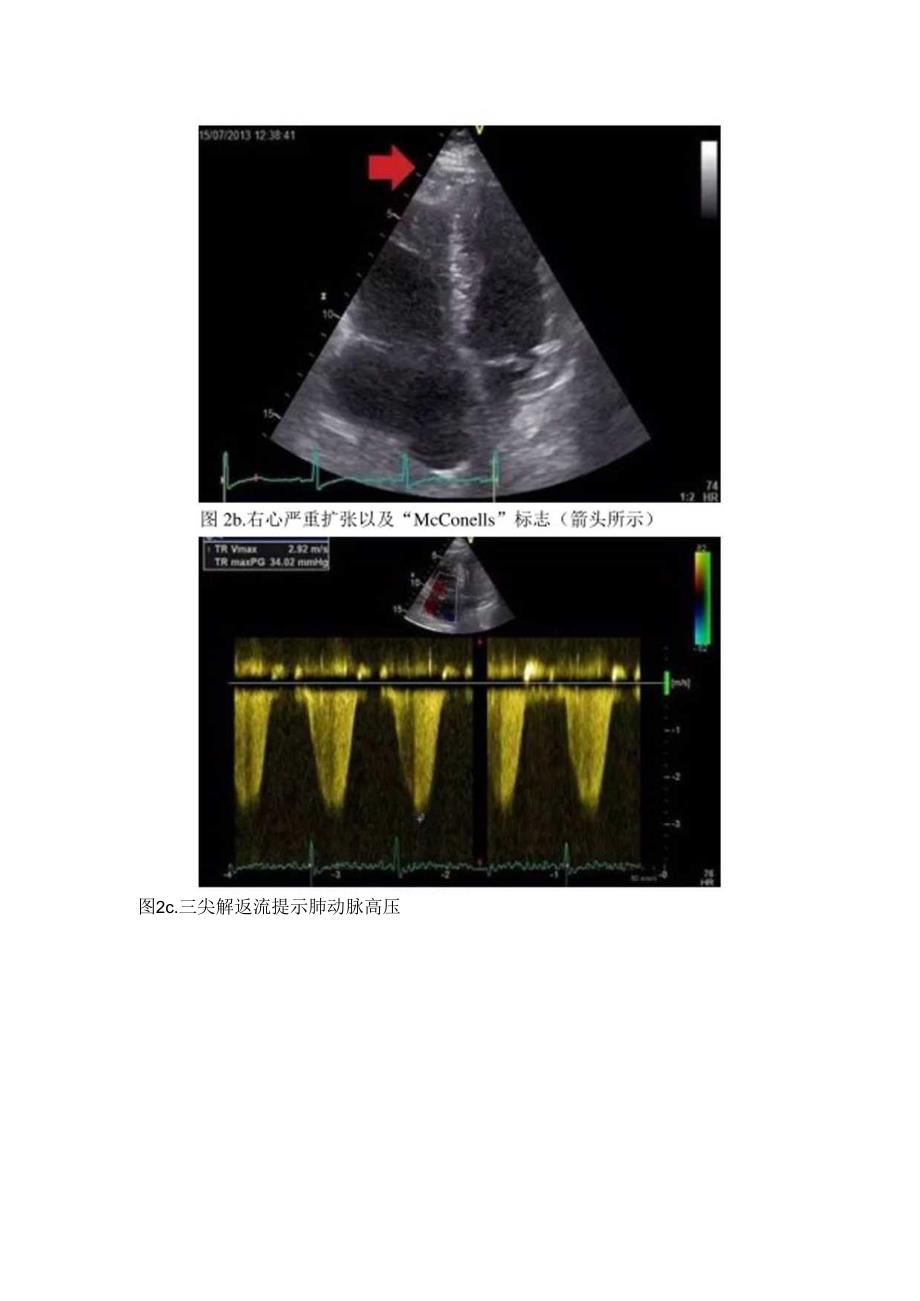

3、,生活方式积极健康.检查中可听到明亮的第二心音,体格检杳可见一例小腿肿胀,但无压痛及红斑。后续,患者血压降至8870mmHg,给予液体驻苏。各项检查结果出来后,没有任何迹象表明该患衣也有I型MI(即个或多个冠状动脉粥样硬化斑块破裂、溃疡、开裂、糜烂或夹乂形成腔内血栓,导致心肌血流量降低或远端栓子形成,最终心肌细胞坏死),因此,终止急性冠脉综合征治疗,进而采用超声心动图观察是否有局部室壁运动异常(RWMA)和右心状况。超声心动图未显示RWMA,只是强调出现“右心应变”(图2)的典型特征.建议行计算机断层扫描(CT)肺动脉造影(CTPAZ肌钙蛋白可能是只是继发原因导致的心肌损伤的反应。CTPA后显

4、示双侧大段肺动脉栓塞(图3)。患者随后开始服用华法林,并出院。图2a.收缩期压力超负荷示空间隔被压扁(箭头所示)图2c.三尖解返流提示肺动脉高压图2d:尖瓣返流继发右心室扩张图3a.肺动脉期主动脉水平CT可清晰示主、右肺动脉内充盈缺损符合肺栓塞表现(箭头所示)图3b,肺动脉期右肺动脉水平CT可清晰示肺动脉充盈缺损(左、右肺动脉符合肺栓塞表现病例讨论随着便携式超声机的普及以及经胸TTE)和经食管(TOE)超声心动图越来越多的应用,其在临床实践中也被广泛认可。肺栓塞(PE)的成像金标准是CTPA,当出现疑似大规模肺栓塞(MPE)患者时,应在一小时内完成检查。多层螺旋CTPA的出现大幅度提高了扫描速